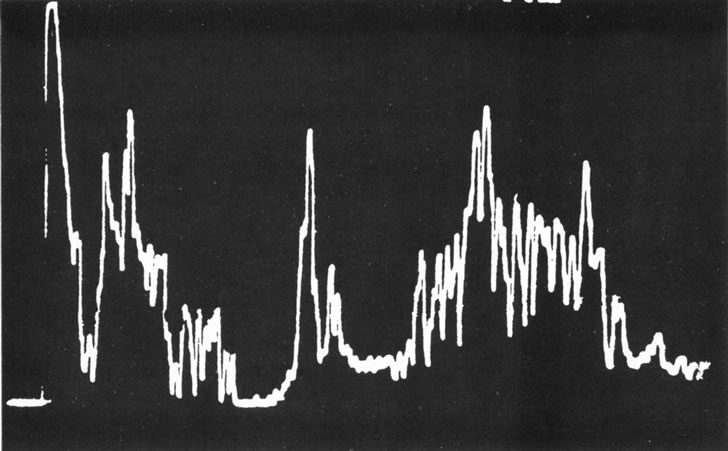

Unfortunately, imaging studies are not always diagnostic. The A- and B-scans shown in Figures 3 and 4 were from a patient with unilateral media opacity referred for evaluation and treatment of a presumed uveal melanoma. Occasionally, if the cataractous lens is scanned tangentially, artifact can occur. A repeat ultrasound at our institution was negative for tumor, and the referral ophthalmologist who performed a cataract extraction noted that no tumor was present and that the patient has an excellent visual outcome. In contrast, the patient shown in Figure 5 was referred with a presumed uveal melanoma with secondary inflammation and a history similar to that described for the patient shown in Figure 111 Ultrasound and CT examinations were not diagnostic. Because the eye was blind and painful, it was enucleated, and an extremely necrotic uveal melanoma was noted histologically. In some necrotic melanomas, the fundus cannot be visualized and the diagnosis cannot be established with imaging studies. Very rarely, a necrotic uveal melanoma can produce sufficient pigment dispersion into the vitreous to obscure the correct diagnosis.12